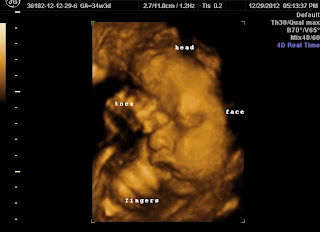

The weekend after Christmas when I was 34 weeks pregnant we traveled to

Buffalo, NY to catch a sneak peak at our little girl.

![]() |

| How our daughter was positioned at 34 weeks |

She gave us a bunch of information about

breech babies; our daughter was Frank Breech, which means her feet were pulled

up by her face, and things our doctor might recommend. And then we waited…